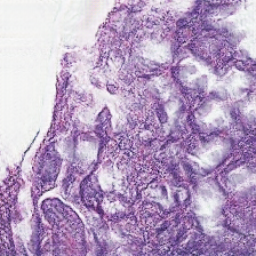

For Target Domain, the MHIST dataset [2] is used (available at https://bmirds.github.io/MHIST/ ), which contains high quality H&E stained histopathology images suitable for learning realistic color and texture distributions.Jana The dataset contains 3,152 H&E images. Some examples are displayed in Figure 1.